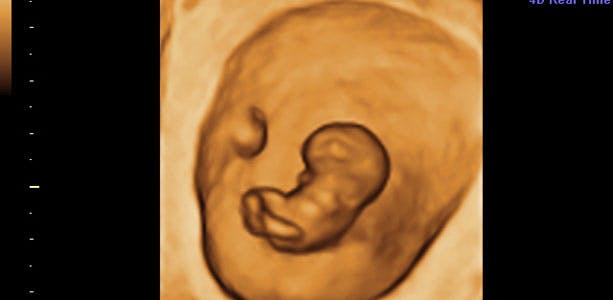

Gravid uge 10: Alle organer er på plads

Du er i uge 10 (også kaldet 10.uge), når du er 9+0 til 9+6. Anlæggene til mælketænder og smagsløg dannes, og sidst på ugen måler dit barn cirka 35 millimeter fra hoved til hale og vejer cirka 15 gram

Alle organer er på plads, men endnu umodne. Baby danner små mængder urin, som bliver en del af fostervandet. Fostervandet har mange vigtige funktioner og tjener blandt andet som bevægelsesmedie for din baby. Anlæggene til mælketænder og smagsløg dannes, og sidst på ugen måler dit barn cirka 35 millimeter fra hoved til hale og vejer cirka 15 gram.